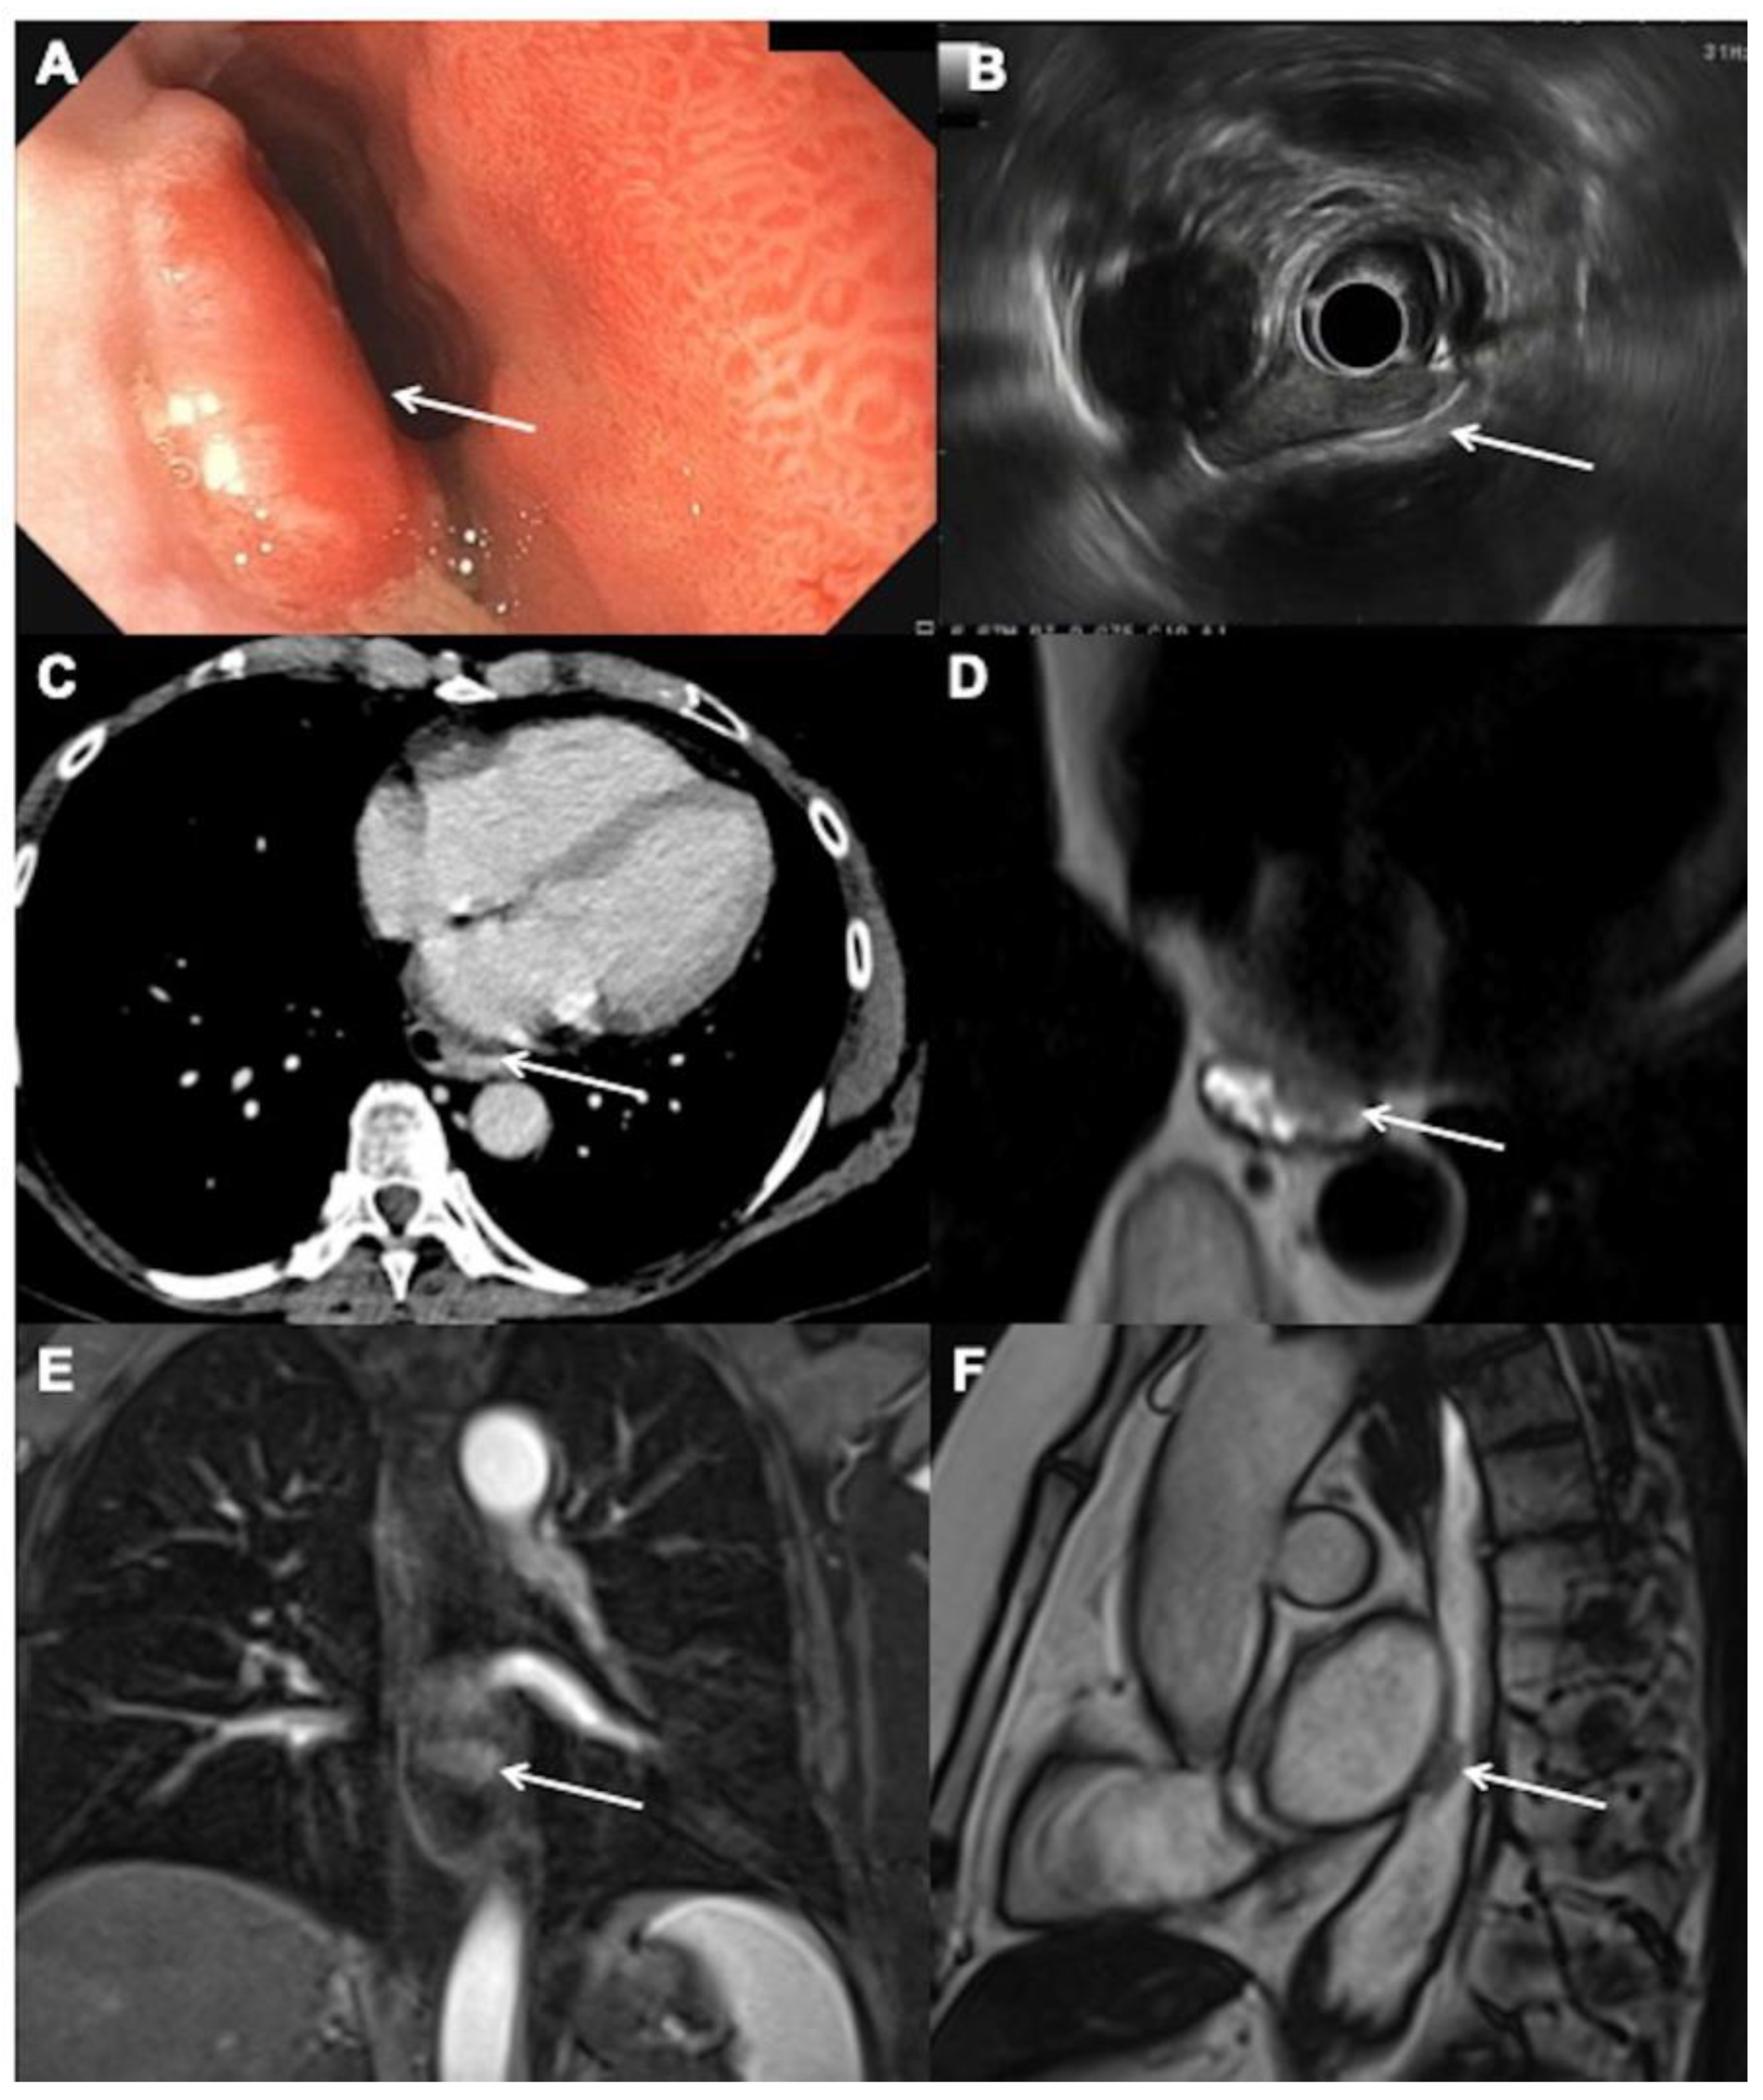

3.1. Initial Tumor (T) Staging

3.2. Node (N) Staging

3.3. Metastases (M) Staging